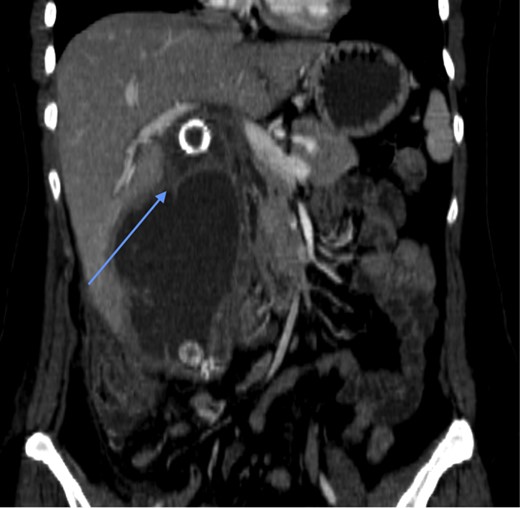

Laboratory investigations (biochemical profile and urinalysis) were all within normal limits. Abdominal CT showed pneumobilia and a 2 cm intraluminal density in the distal ileum with resultant small bowel obstruction (Figs 1 and 2). She underwent emergency laparotomy and enterolithotomy followed by a smooth postoperative course (Figs 3 and 4). The CT scan taken elsewhere and just prior to the emergency cholecystecomy 12 months earlier was reviewed; this demonstrated a markedly distended gallbladder with irregular wall thickening and severe pericholecystic fat stranding consistent with a gallbladder empyema measuring 16 cm × 9.0 cm. There were also multiple gallstones with the largest two measuring 2 cm at the neck of the gallbladder and the other, 2.0 cm in diameter at the fundus of the gallbladder, respectively. There was a narrower, septum-like area between the neck and grossly distended empyema (Fig. 5)

CT scan prior to cholecystectomy, 12 months earlier, showing calcified gallstones within gallbladder empyema and a septum-like narrowing (arrow) between the neck and the grossly distended empyema.

GSI develops only in 0.3–0.5% of patients with cholelithiasis (3). The typical patient who presents with GSI has a history of acute or chronic cholecystitis at which time the gallbladder adheres to the duodenum leading to the formation of a fistula. The vast majority (96.5%) are associated with a cholecystoduodenal fistula (1). Subtotal cholecystectomies are done when there is severe inflammation of the gallbladder and this can be a safe option to avoid dissection of Calot’s triangle (4). However, after such a procedure it must be ensured that the remnant is free of gallstones, as there have been complications such as choledocholithiasis, persistent biliary fistula, gallstone pancreatitis and acute cholecystitis related to such a procedure (5). We believe that, in our case, the gallbladder was transected between the neck and the grossly distended empyema, leaving a large gallstone at the neck (Fig. 5). Subsequent stump cholecystitis with fistula formation would have delivered the 2 cm gallstone into the gut causing GSI, since the calcified stone at the gallbladder neck 1 year before is very similar to the one obstructing the ileum.